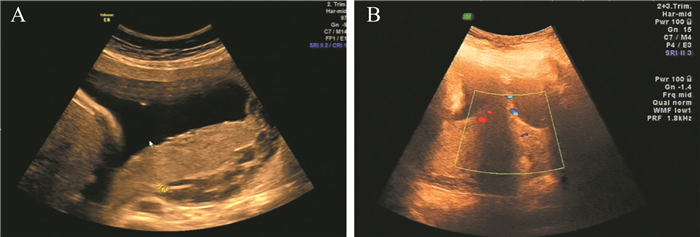

病例资料 一、病史与体格检查患者女,34岁。因停经37周,阴道流血半小时于2016年11月21日急诊收入院。患者平素月经规则,月经周期30 d,持续7 d,末次月经2016年3月5日,孕期无腹痛及阴道流血。2017年6月1日患者在本院彩色多普勒超声(彩超)提示NT值在正常范围内。2017年8月23日产科超声示孕24周,胎盘位于后壁,胎盘下缘贴近宫内口,提示胎盘低置状态。2016年10月25日产科彩超:宫内妊娠,33+周大小,胎盘面积大,部分性前置胎盘声像(图 1A)。2017年11月11日产科彩超:宫内妊娠,胎盘面积大,前置胎盘声像(图 1B)。患者入院当日下午5点无明显诱因出现阴道出血,色鲜红,量约1 000 ml,无下腹痛,无阴道流液,自觉胎动正常。孕产史:孕3产1流产1,2009年因胎膜早破剖宫产1子。

图 1 一例凶险性前置胎盘患者的产前B超检查结果 A:2017年10月25日产科彩超示宫内妊娠,33+周大小,胎盘面积大,几乎布满整个后壁、左侧壁、右侧壁,厚约27 mm,成熟度Ⅰ度,胎盘下缘完全覆盖宫颈内口,符合部分性前置胎盘声像;B:2017年11月11日产科彩超示宫内妊娠,胎盘面积大,几乎布满整个后壁、左侧壁、右侧壁,厚约32 mm,成熟度Ⅰ度,胎盘下缘完全覆盖宫颈内口,符合前置胎盘声像 |